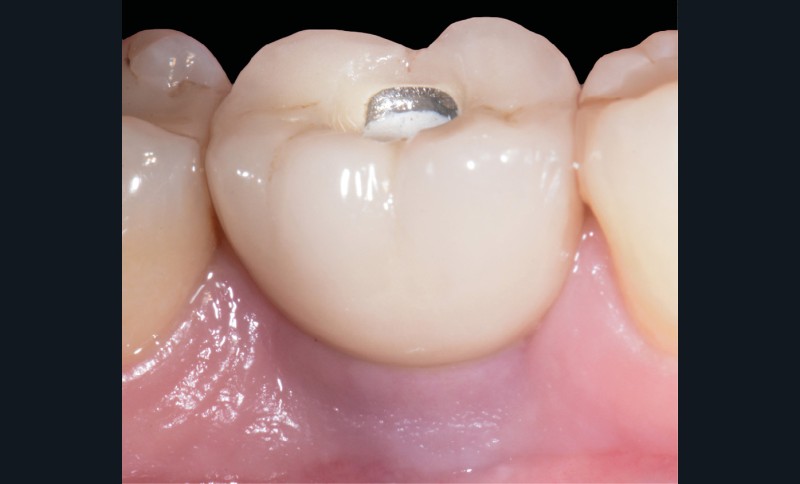

Les critères qui permettent de diagnostiquer une péri-implantite sont aujourd’hui bien établis, les voici rappelés : signes cliniques d’une inflammation péri-implantaire (gonflement, rougeur, saignement au sondage et/ou suppuration) (fig. 1a), perte osseuse péri-implantaire au-delà de celle constatée après la cicatrisation « initiale » (fig. 1b), augmentation de la profondeur de poche au sondage en comparaison de la profondeur de poche identifiée lors de la mise en place de la restauration prothétique [2, 23]. En l’absence de documents radiographiques préexistants, une perte osseuse supérieure ou égale à 3 mm en association avec un saignement au sondage et une profondeur de poche au sondage supérieure ou égale à 6 mm permet également de poser le diagnostic de péri-implantite [23].